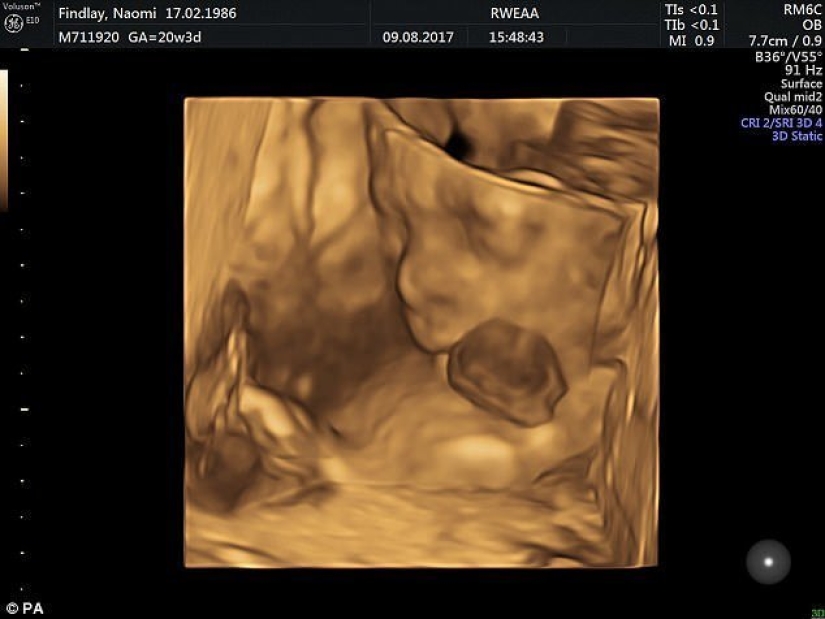

Por Pictolic https://www.pictolic.com/es/article/medicos-britnicos-salvaron-a-una-nina-que-naci-con-el-corazn-fuera.htmlLa pequeña Vanillope Hope Wilkins nació con un defecto extremadamente raro: ectopia del corazón. Con esta patología, el corazón humano se encuentra fuera del cuerpo. Varias docenas de cirujanos lucharon por su vida y, para alegría de todos, la niña sobrevivió.

Los padres de la niña se enteraron de la ectopia en la novena semana de embarazo, pero la madre se negó a abortar, a pesar de las persuasiones de los médicos.

De acuerdo con los resultados de las pruebas, el bebé no tenía anomalías cromosómicas. Los especialistas decidieron dirigir todos sus esfuerzos para salvar al niño. Luego se reunió un gran equipo de obstetras, neonatólogos, cardiólogos y otros especialistas.

Según las estadísticas, más del 90% de los recién nacidos con ectopia cardíaca nacen ya muertos o mueren durante los primeros días de vida. Esta patología es extremadamente rara — varios casos por millón. En la práctica, hay muy pocas posibilidades de sobrevivir a la ectopia.

Se esperaba que la niña naciera el 25 de diciembre, pero los médicos decidieron ir a lo seguro y la extrajeron del útero de su madre por cesárea el 22 de noviembre.

Ya 50 minutos después del nacimiento, el bebé fue enviado a la sala de operaciones. 50 médicos participaron en la intervención quirúrgica en dos etapas. Como resultado de dos operaciones complicadas realizadas en el primer y séptimo día de vida del niño, el corazón se trasladó de manera segura al tórax.

La niña no tiene esternón, por lo que los cirujanos le hicieron una pequeña incisión en el pecho y la estiraron con un anillo de plástico para crear más espacio para el corazón. El órgano de latido, cubierto con una membrana protectora temporal, se colocó sobre el orificio. Durante los siguientes nueve días, Vanilope se acostó boca arriba en la unidad de cuidados intensivos, y su corazón gradualmente, bajo la influencia de la gravedad, se hundió de forma independiente en el agujero en su pecho.

Para el 1 de diciembre, el corazón de Vanillope se había movido completamente al pecho. Se retiró el anillo de plástico y se cubrió el orificio en el tórax con un parche de membrana transpirable permanente para evitar que la piel creciera hacia el corazón. Luego, los extremos de las costillas del niño se unieron mediante una malla especial para crear una especie de jaula que protegía el corazón en lugar del esternón. Al final, los cirujanos hicieron incisiones laterales bilaterales en la piel de la niña, lo que permitió tirar de la piel sobre el área de la incisión y coserla.